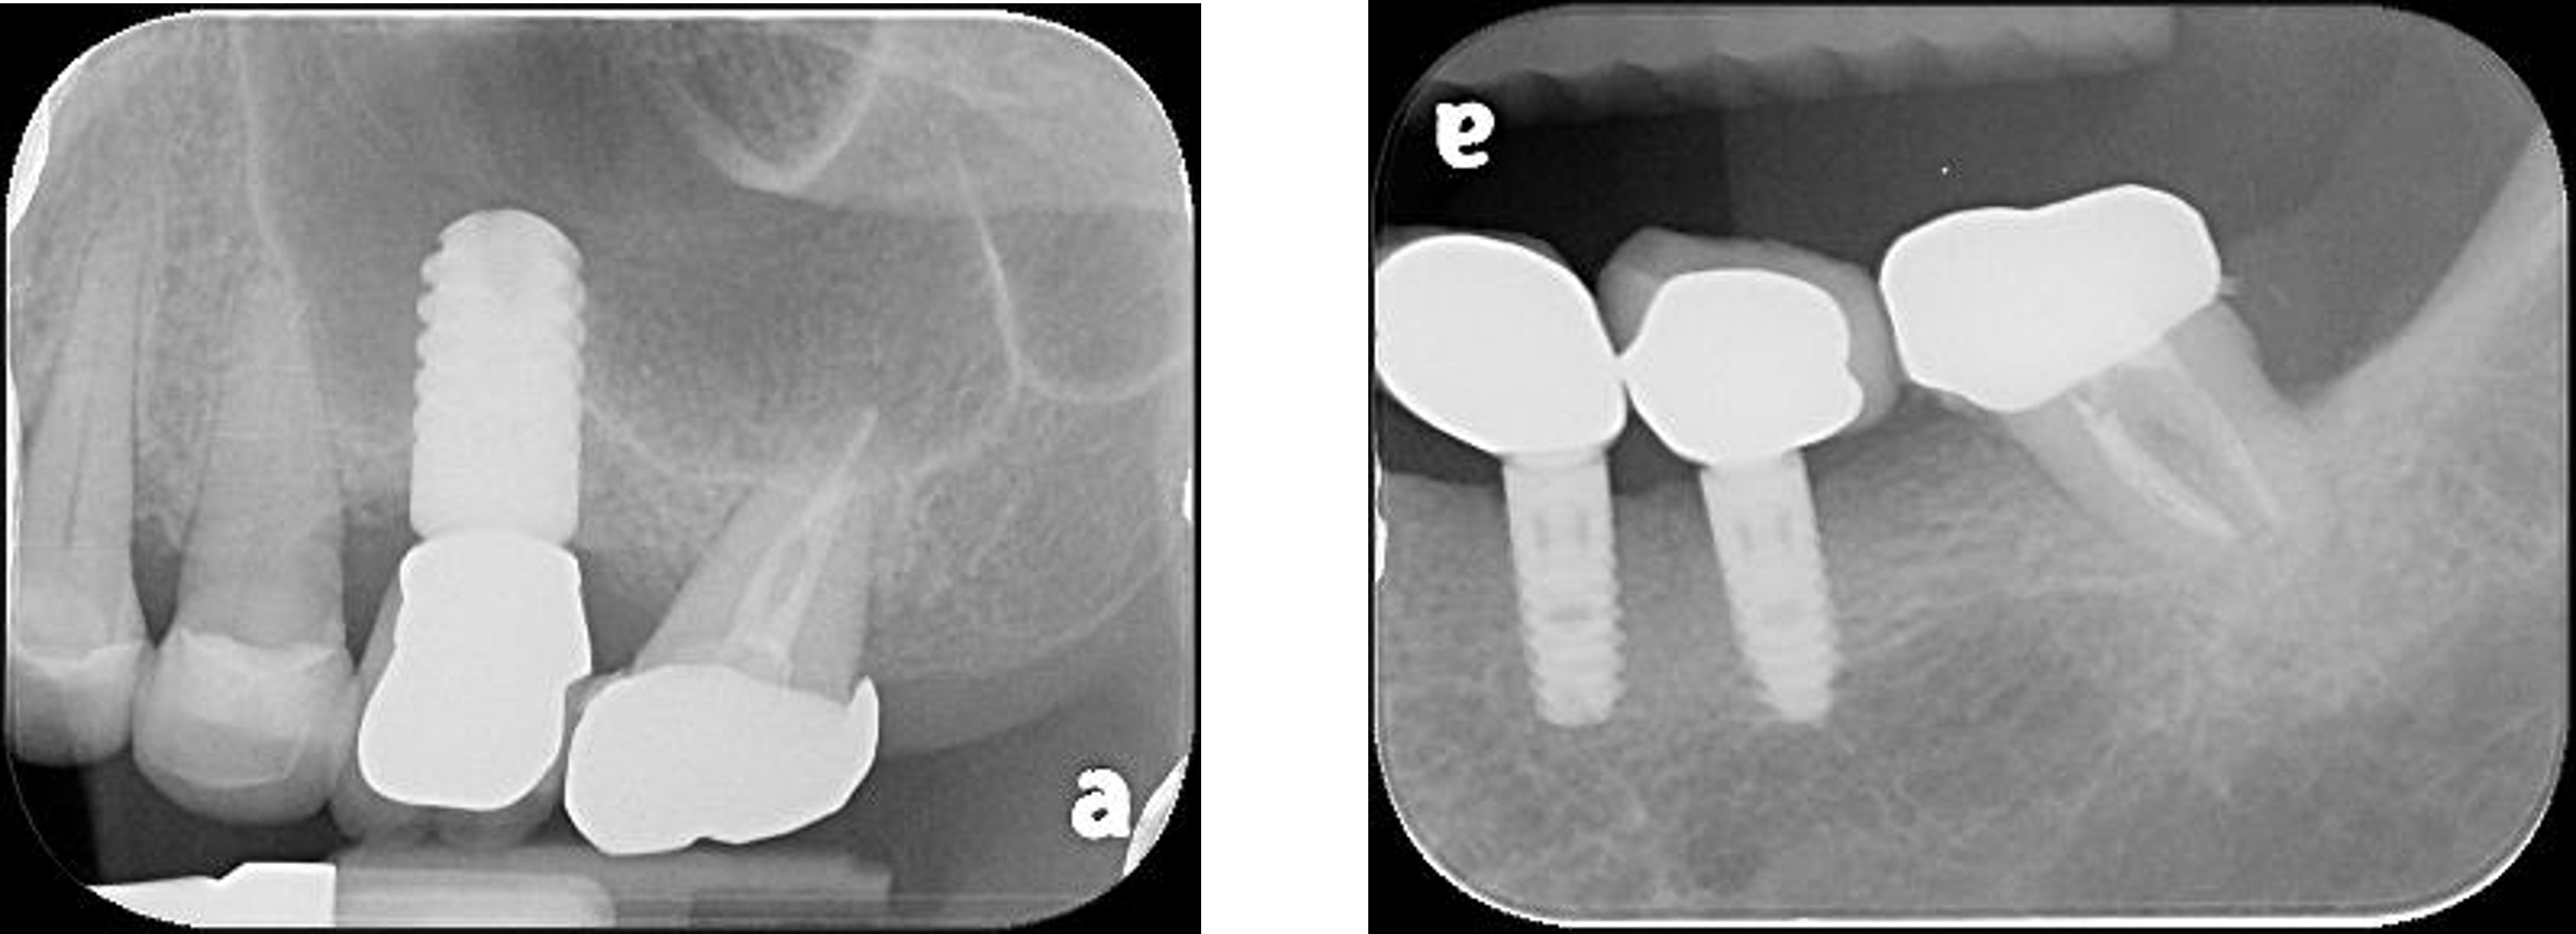

治療前,左上及左下第二大臼齒根管鈣化

顯微根管治療:#37

顯微根管治療:#27